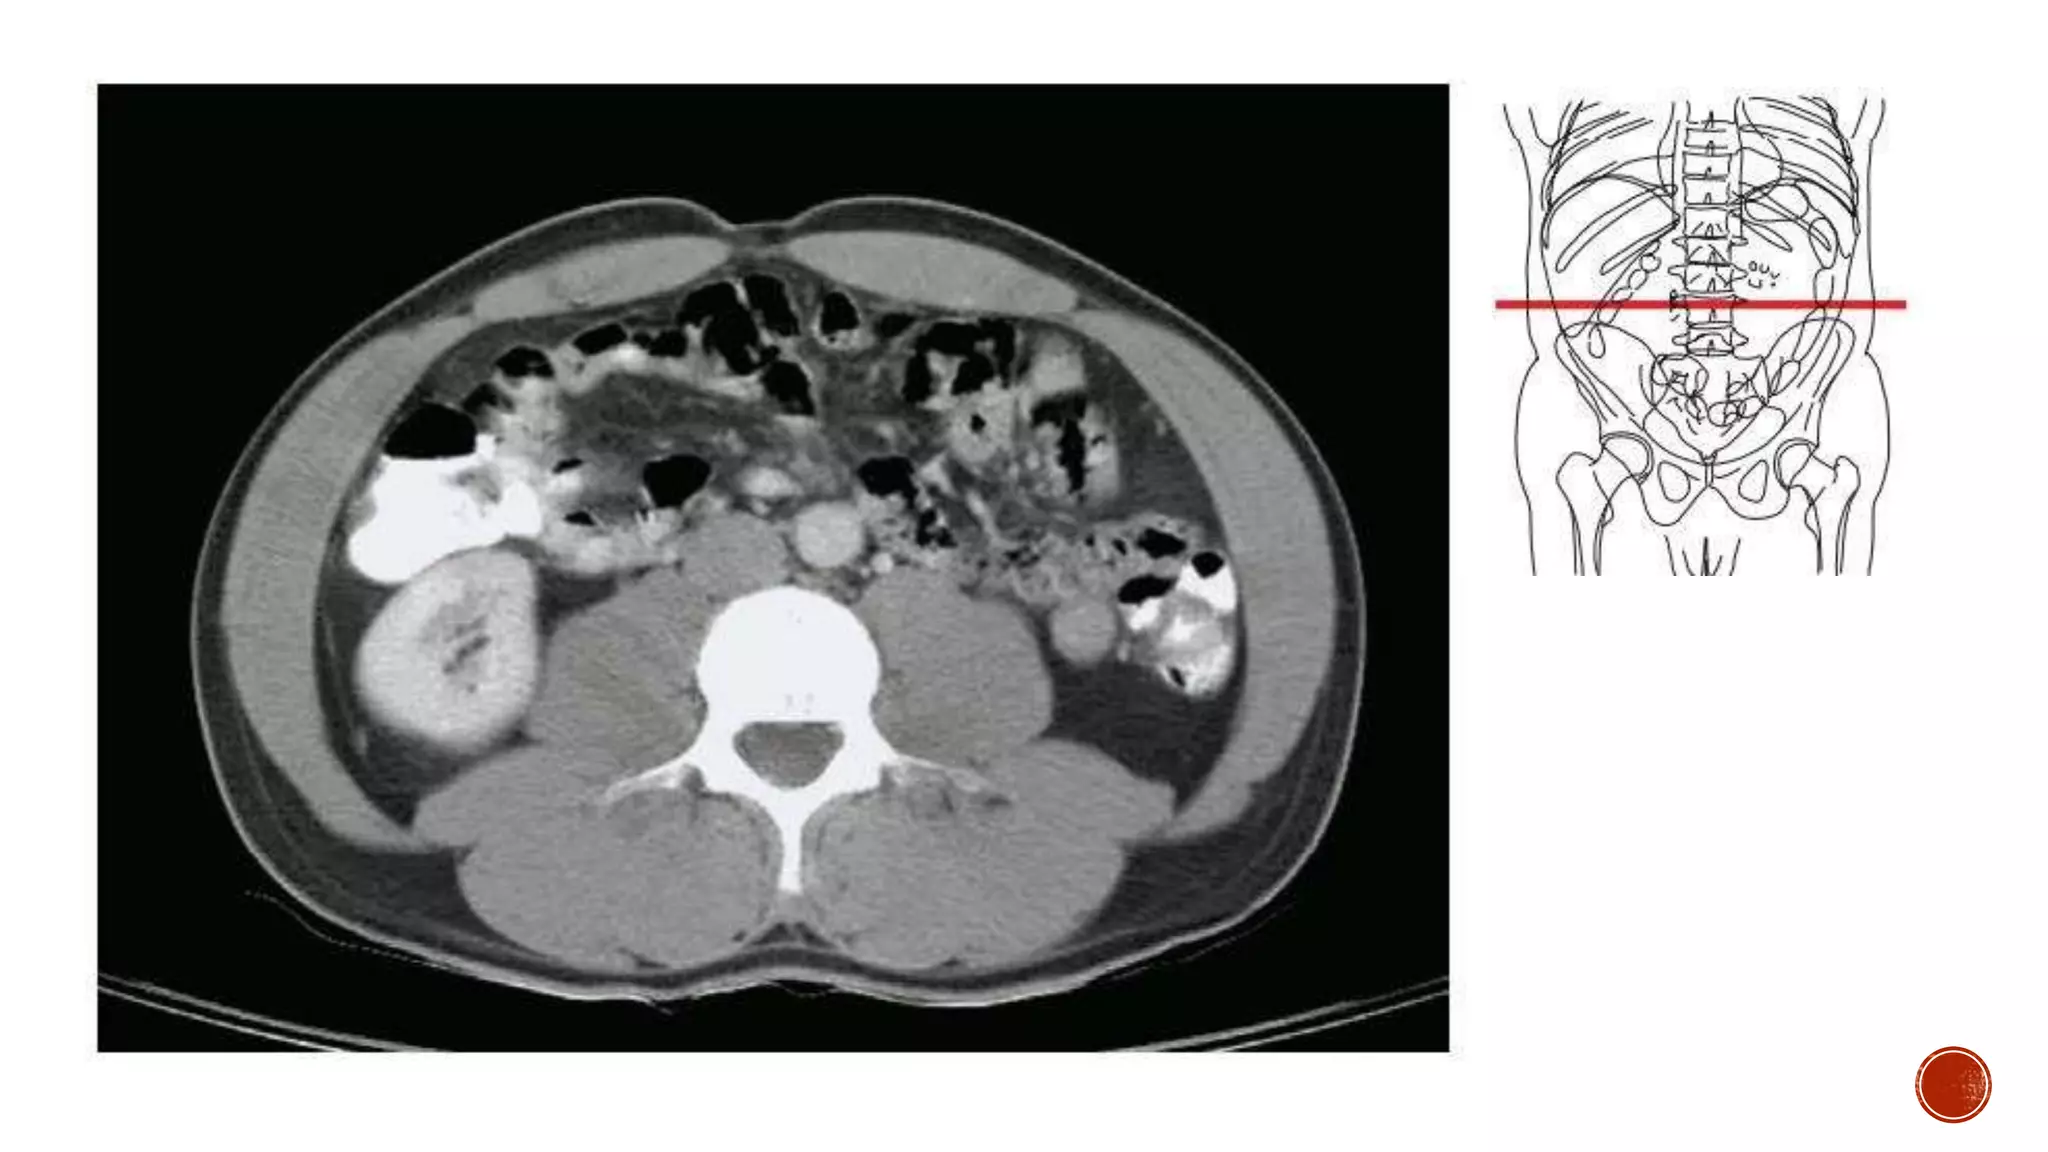

The document describes the anatomy of the abdomen and pelvis region of the human body. It lists over 40 structures and their locations, including major organs like the liver, kidneys, intestines, blood vessels and muscles of the abdominal wall and pelvis. The structures are grouped into sections focusing on different anatomical areas like the abdomen, retroperitoneum, pelvis and gluteal region.